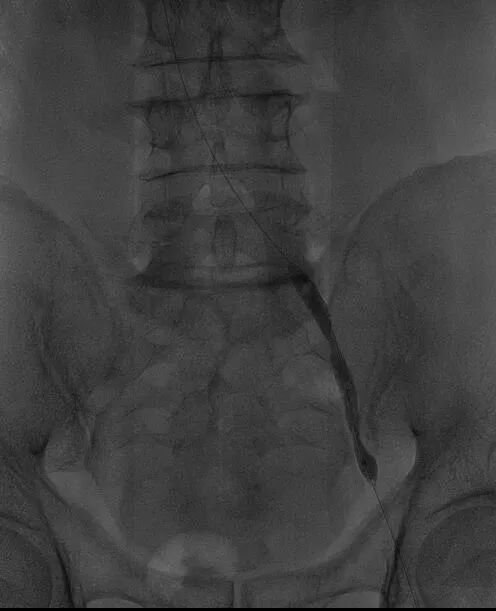

经过全面评估和术前准备,团队为李叔叔制定了“左下肢髂静脉造影+髂静脉球囊扩张成形术”的个性化手术方案。

手术过程中,田轩团队凭借精湛的介入技术,经大隐静脉入路穿刺,成功开通闭塞的髂静脉。